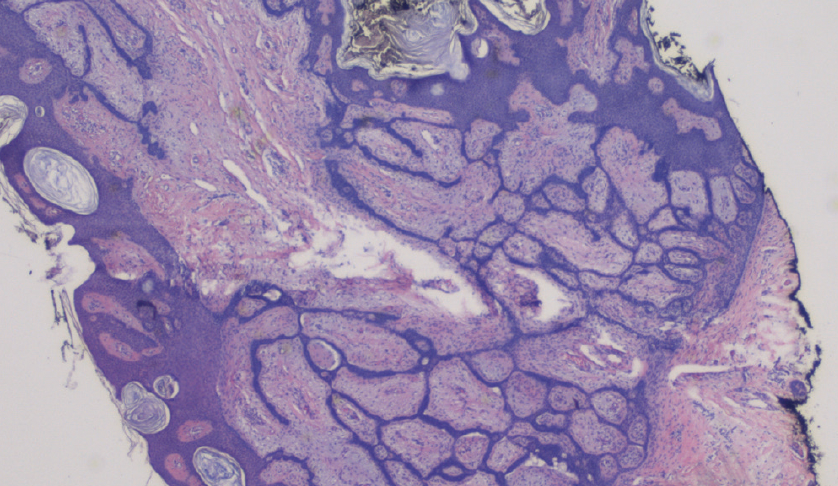

This patient’s skin growth was confirmed via biopsy to be fibroepithelial basal cell carcinoma (BCC), which is characterized as a rare subtype of BCC known as fibroepithelioma of Pinkus (FeP). (Figure 2)

Histopathologic findings may reveal tumor islands and anastomosing strands of basaloid, palisading cells residing in a fibromatous stroma.4 These downward projections of basaloid strands may follow a fenestrated pattern and extend as deep as the reticular dermis.2 (Figure 3) Like the typical BCC, there may be palisading, columnar cells bordering the tumor islands, as well as clefts separating the fenestrations and stroma filled with mucin.2 (Figure 4) Reported to grow over the course of 8 years, these lesions have a low likelihood of metastasis, and the prognosis is generally favorable.3 Tools, such as dermoscopy and reflectance confocal microscopy, are increasingly used to distinguish subtle, fine characteristics among different neoplastic skin processes that appear clinically similar to the naked eye. However, obtaining histopathologic confirmation through biopsy is necessary because these skin growths may clinically simulate amelanotic melanoma, among other life-threatening cutaneous neoplasms.4